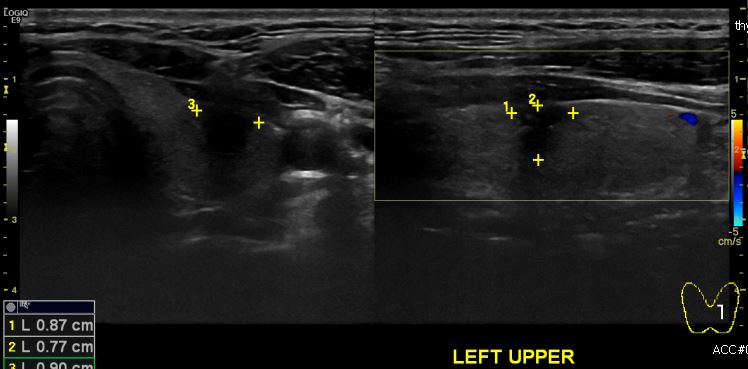

상기환자 목의 통증으로 내원하신 40대 남성분으로 본원 갑상선 초음파 시행 후  좌측 갑상선 상측에 의심스러운 멍울 세침검사 시행하여 좌측 갑상선 유두암 진단 되었습니다.